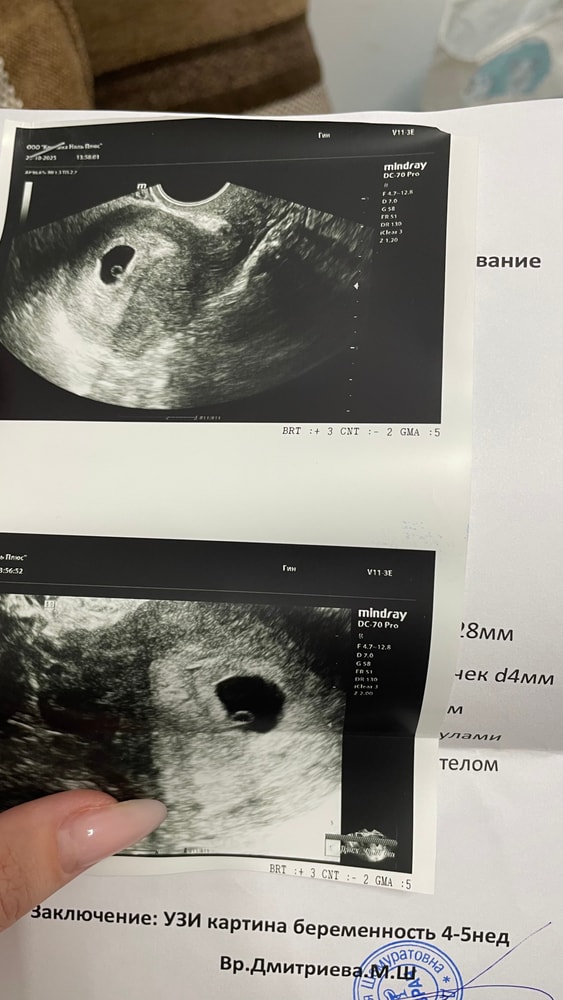

Напомню, что 4 дня назад на узи было пустое плодное яйцо 8мм и все. Думала, что маленькое все для, начала загоняться и решила, что все таки переделаю для себя.

По сегодняшнему узи )) ПЯ 28мм, желточный мешочек 4мм, ктр 2мм, еще совсем крошечка🙏🏻 через полторы недельки пригласили на контроль сб

По крайней мере я успокоилась, пя выросло, жм появилось, крошечка растет ♥️